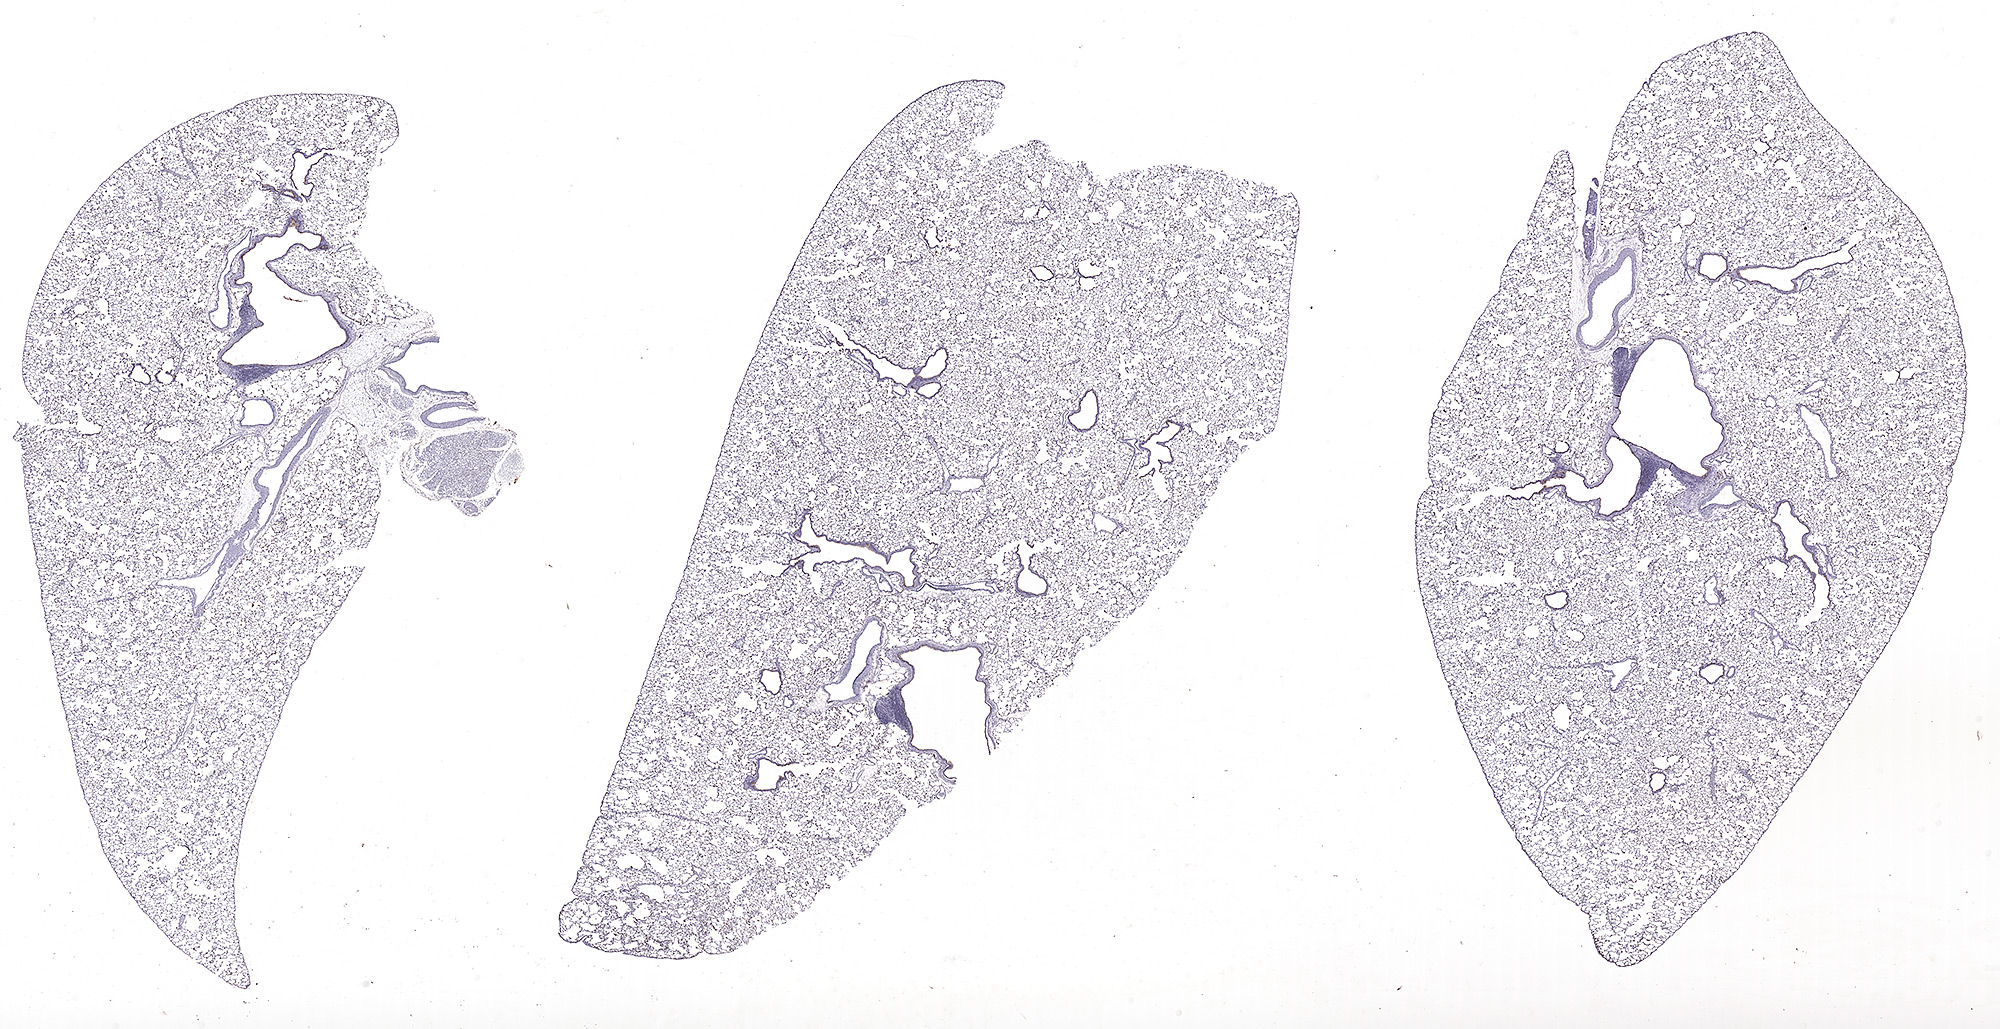

SP-A: Immunoperoxidase staining of formalin-fixed, paraffin-embedded mouse lung showing cytoplasmic staining in the bronchiolar epithelium and type II cells.